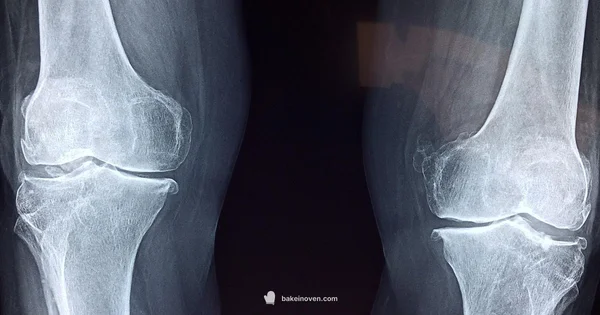

Baker's cyst is a fluid-filled swelling behind the knee caused by excess joint fluid from the knee.

A Baker's cyst, also known as a popliteal cyst, is a fluid-filled sac that forms behind the knee. It develops when the knee joint produces extra synovial fluid, often in response to conditions like arthritis, injury, or meniscal tears. The cyst is connected to the knee joint through a small channel, which means changes in knee health can cause the cyst to fluctuate in size. For most people, a Baker's cyst is not a separate disease so much as a sign that the knee is under stress. The fluid collection can press on nearby structures, sometimes causing swelling, stiffness, or a feeling of fullness behind the knee. In many cases, the cyst resolves on its own with rest and treatment of the underlying knee problem. Others may need medical procedures to reduce swelling or address persistent symptoms. When you read about Baker's cysts, remember they are a knee-centric condition; elbow, hip, or other joints can swell for different reasons, and what looks like a cyst in one joint is often a different issue in another.

Diagnosis: what your clinician will check

Diagnosing a Baker's cyst involves a careful history and physical examination, followed by imaging when necessary. A clinician will assess knee function, range of motion, swelling patterns, and the presence of joint effusion. For a suspected elbow swelling, the clinician will examine the elbow for bursitis, tendon problems, infection, or a soft tissue mass, and may review the knee health history to see if an underlying knee problem could be contributing. Imaging studies such as ultrasound are useful to distinguish cystic fluid from solid masses, while MRI provides detailed information about joint structures and potential connections to the knee. In some cases, aspiration of knee joint fluid and analysis of the fluid can help confirm the diagnosis and rule out infection. In the rare instances where a cyst seems to involve the elbow but could be a signaling of a knee-related process, the clinician may perform additional tests and correlate with knee imaging. Early and accurate diagnosis improves outcomes and reduces the risk of persistent swelling or discomfort.